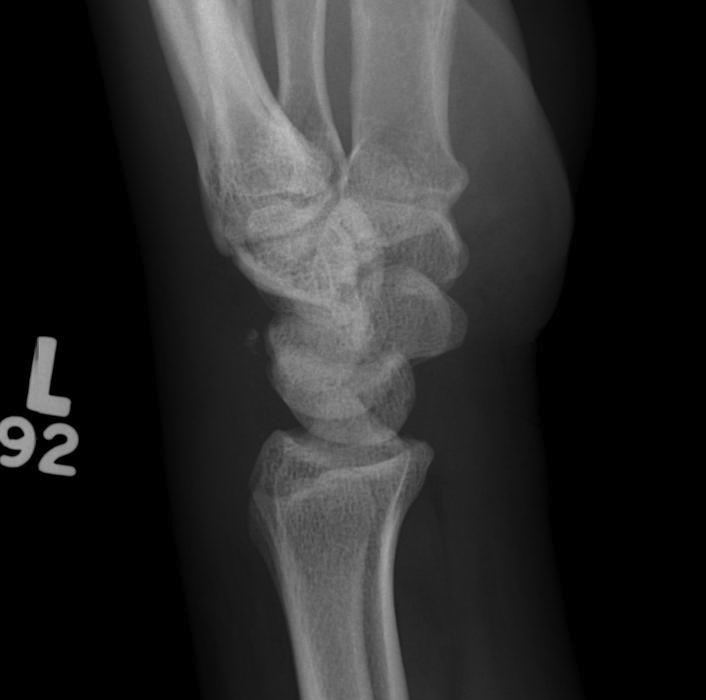

X-ray

Disruption of Gilula's 3 smooth carpal arcs

Progressive Injury

1. Capitate dorsal

- lunate remains with radius

- lunate looks triangular on AP

2. Lunate dislocates

- usually volar